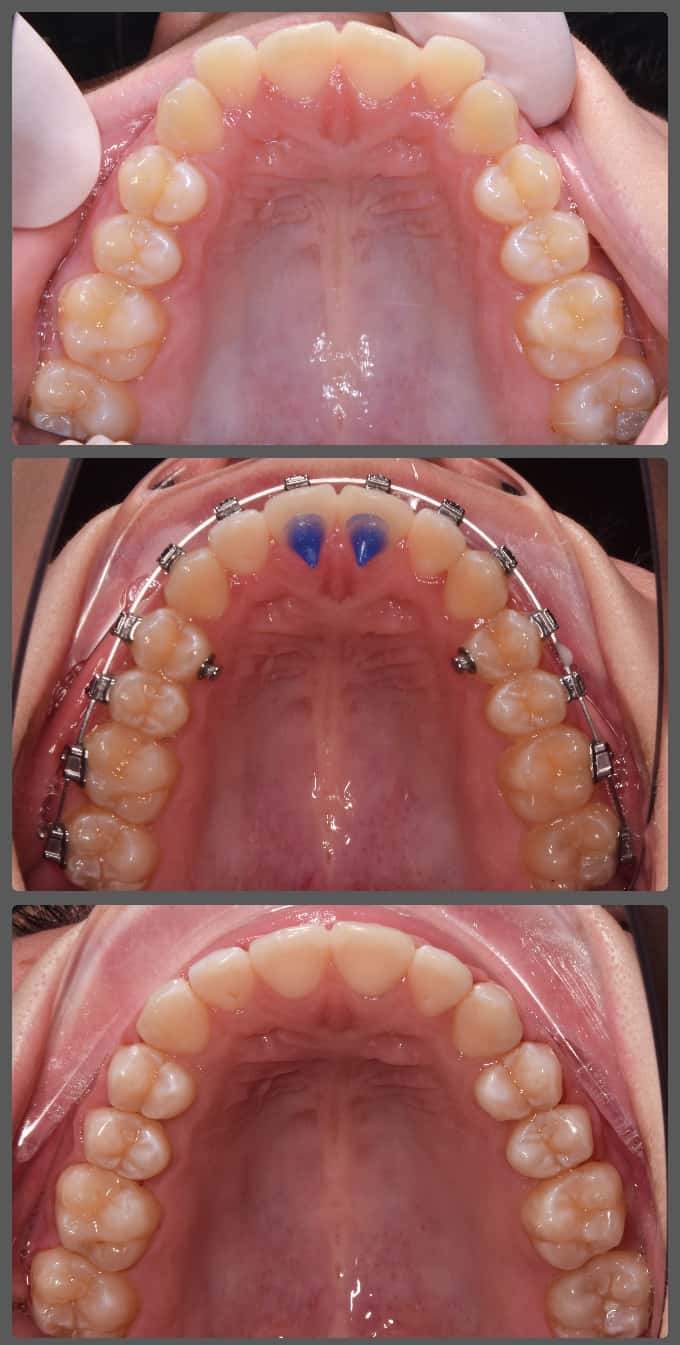

Bettinát a Semmelweis Egyetemen kezeltem, ahol az első fogszabályozási konzultáció alkalmával kiderült, hogy az enyhe torlódása mellé egy jelentős felső állcsontszűkület is társul. Jobb oldalon keresztharapás volt látható. A szűk felső fogív az alsó állkapocs kényszeres elcsúsztatását eredményezte, ami a jelentősen jobbra tolódott alsó középvonalon is jól látszik. A megfelelő diagnózis felállítása után két fázisú (előkezelés, majd rögzített készülékes kezelés) terápia mellett döntöttünk. Bettina kezelését az I. fázisban hyrax készülékkel kezdtük, ennek segítségével megtágítottuk a felső állcsontot, fogívet. A 8 hónapos I. fázist egy gyors, 14 hónapig tartó alsó-felső hagyományos rögzített készülékes kezelés követte. A fix készülékes kezelés során harapásemelőket és intermaxilláris gumihúzást is alkalmaztam a tökéletes végeredmény elérése érdekében. A két fázisú kezelés 22 hónapig tartott. Bettina folyamatos, töretlen együttműködésének köszönhetően úgy hiszem, hogy különösen szép végeredményt értünk el esztétikai és funkcionális szempontból egyaránt.